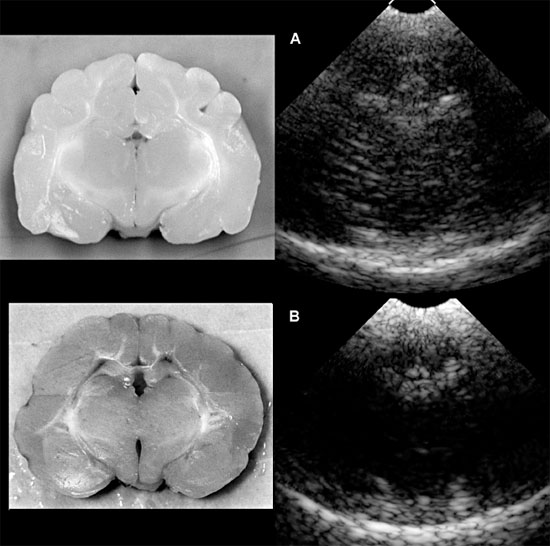

Cerebrocortical hypoplasia has been reported to be caused by loss or abnormal proliferation and/or migration of cortical neurons because of specific inherited abnormalities, toxins, in utero infections, or vascular insults. In some cases, lack of development shown as decreased detail of the brain echotexture might be apparent with ultrasonography either through a persistent fontanel or by viewing the brain through the foramen magnum (Figure 1.21).

Figure 1.21. Sonograms of a normal kitten and a kitten with abnormal brain development. A: Sonogram of a normal 1-week-old kitten next to the gross transverse section from a normal 1-month-old kitten. B: Sonogram of an 8-week-old kitten with severe neurological deficits caused by cerebrocortical dysplasia and abnormal myelinization. The sonogram shows a lack of detail compared with the normal kitten. The cause of this lack of detail is unknown. A gross transverse section from the kitten is seen on the left. Note the decreased visualization of white matter tracks and decreased depth of sulci.